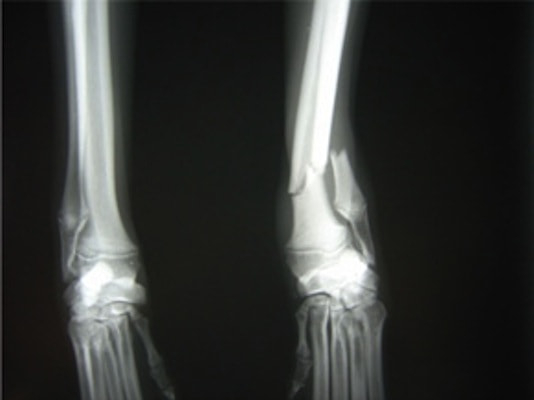

術前レントゲン

他院にて左大腿骨遠位の成長板骨折(salter-harrisⅠ型)が認められており、治療相談を目的として来院。当院にて、キルシュナーワイヤーを用いたピンニングにより骨折部位の整復を行いました。術後の経過は良好で、現在も経過観察中です。

ペルシャ猫 11ヶ月齢 雄